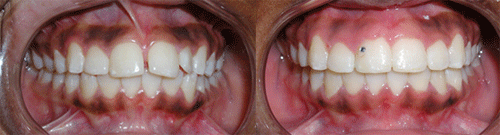

Protruded teeth (bucked teeth) happen when either the upper jaw is too far forward, the lower jaw is too far back, or a combination of both. Expert analysis allows us to determine the cause of the protrusion, and the most effective treatment plan.

With this type of bite, the front teeth are very protuded, and makes these delicate teeth highly prone to trauma, injury, and even premature tooth loss.

We have a number of different options and appliance types for correcting protruded teeth. The photos below illustrate protruded teeth, and the corrections in our patients.